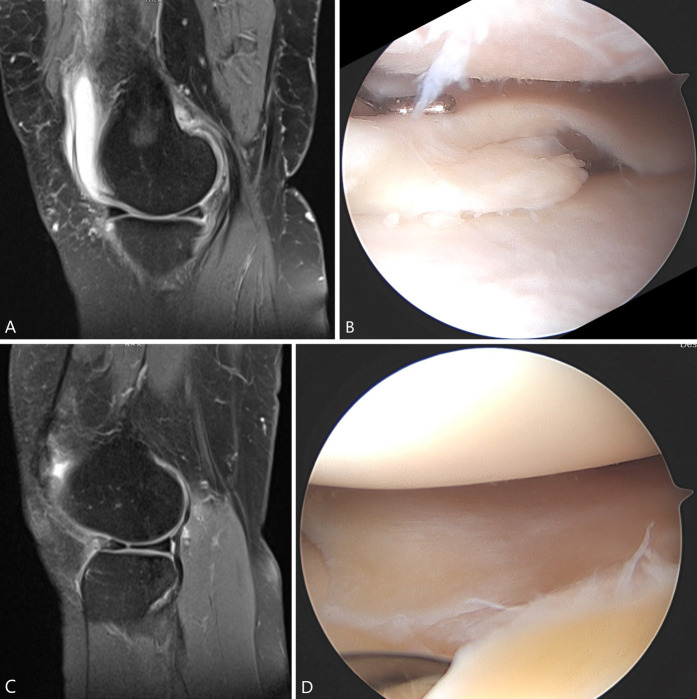

Fig. 2.

A-D These case examples demonstrate application of the ISAKOS classification system: (A) Sagittal T2-weighted MRI sequence and (B) arthroscopic image demonstrating a complete medial meniscal tear involving Zone 3 of the posterior and middle thirds, with vertical flap tear pattern, with degenerative tissue quality, measuring approximately 1 cm, for which approximately 20% of the meniscus was excised. (C) Sagittal T2-weighted MRI sequence and (D) arthroscopic image demonstrating a complete lateral meniscal tear involving Zone 1 of the middle third, not central to the popliteal hiatus, with radial tear pattern, with nondegenerative tissue quality, measuring approximately 1.5 cm, for which approximately 20% of the meniscus was excised (following debridement of the central portion and repair of the residual tear). Reproduced from the Journal of ISAKOS: Joint Disorders & Orthopaedic Sports Medicine, Shah J, Hlis R, Ashikyan O, et al., volume 5, pages 201-207, 2020, with permission from BMJ Publishing Group Ltd.